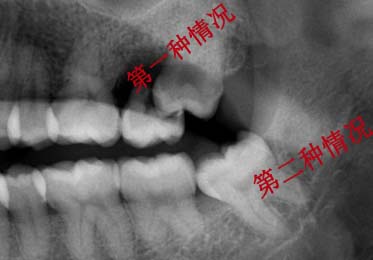

很多人因为有严重的口腔的问题,导致牙齿不得不拔掉。拔牙虽然是个小手术,但如果不稍加注意的话,会给口腔带来感染。那么拔牙当天要注意哪些问题?下面请看医生为您作详细介绍。

拔牙看起来就是个小手术,但患者应选择正规的医院进行拔牙,这才不会感染拔牙后牙排会出现一个很大的缝隙,我们需要进行镶牙才防止缝隙的病变及牙周的萎缩。通常我们推选患者使用种植牙来进行牙齿修复。